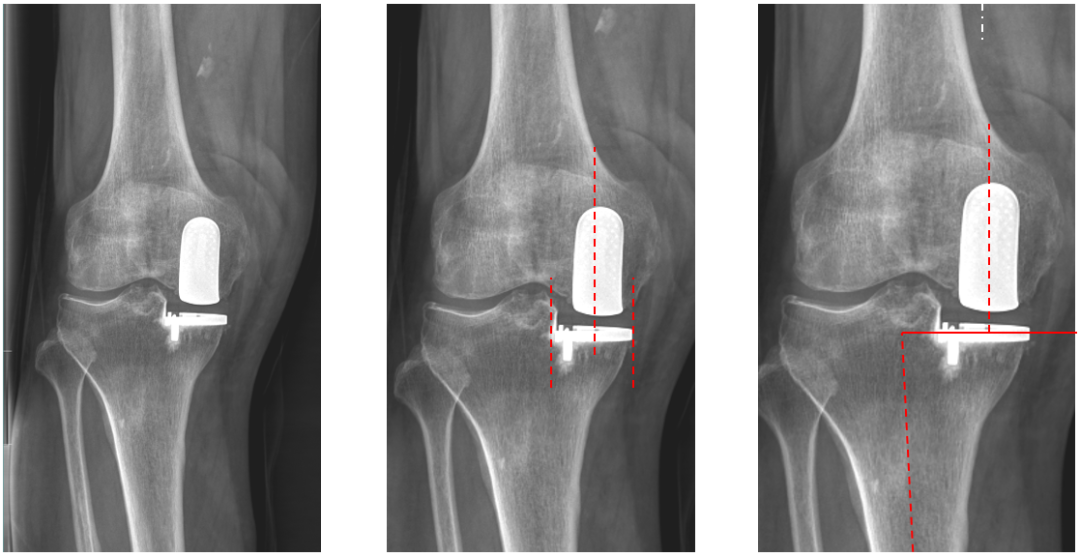

三、内侧LINK:registered: SLED假体位置

(全聚乙烯设计胫骨平台假体)

正位片标准胫骨和股骨假体位置

AP位假体位置:胫骨假体无内外翻,内侧缘超出胫骨平台内侧缘1mm; 股骨假体长轴与胫骨假体垂直,中线一致。

侧位片标准胫骨和股骨假体位置

侧位片假体位置:胫骨假体后倾3°,与胫骨平台前后缘齐平,股骨假体后倾40°,假体后缘与股骨后髁齐平。

胫骨假体厚度合适

胫骨垫片厚度合适:术前内翻畸形基本矫正,残留2-3°内翻。

股骨假体偏内放置,胫骨假体偏大

AP位胫骨与股骨假体位置:胫骨假体内侧悬挂>2mm,股骨假体中轴线与胫骨假体中线不一致,偏内侧。

股骨假体偏大且过度屈曲

侧位片假体位置:股骨假体后倾45°,假体后缘超出股骨后髁3mm, 胫骨假体后倾3°,与胫骨平台前后缘齐平。

四、外侧LINK:registered: SLED假体位置

AP位假体位置:胫骨假体外翻3°,内旋10°,外侧缘与胫骨平台外侧缘齐平; 股骨假体长轴与胫骨假体垂直,中线一致。

侧位片假体位置:胫骨假体后倾5°,与胫骨平台前后缘齐平,股骨假体后倾35°,假体后缘与股骨后髁齐平。

股骨假体偏内放置

AP位胫骨与股骨假体位置:股骨假体无内外内翻,中轴线与胫骨假体中线不一致,偏内侧。

侧位片股骨假体后倾不足

侧位片假体位置:胫骨假体后倾3°,完全覆盖胫骨平台前后缘,股骨假体后倾30°,股骨后髁覆盖不足。

胫骨假体偏厚

胫骨垫片厚度合适:术前外翻畸形矫正至轻度内翻。